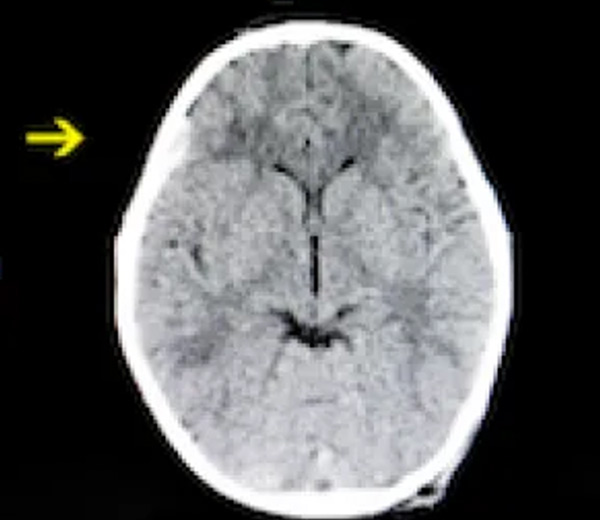

A 42-year-old patient was seen in the emergency department for a headache after a fall. The CT scan was normal as per tele-radiology. The patient left and went home to a different city. The next day on follow up the patient was found to have a subdural hematoma, which was missed on CT. When the doctor called, the patient’s headache had worsened, and he was somnolent. He coordinated the emergency response with Telemedicine911 to take the patient to their affiliated facility with neurosurgical operating rooms. The patient completed the procedure within the hospital system, had a short post op stay, and was discharged home to follow up.

Image not from actual case.